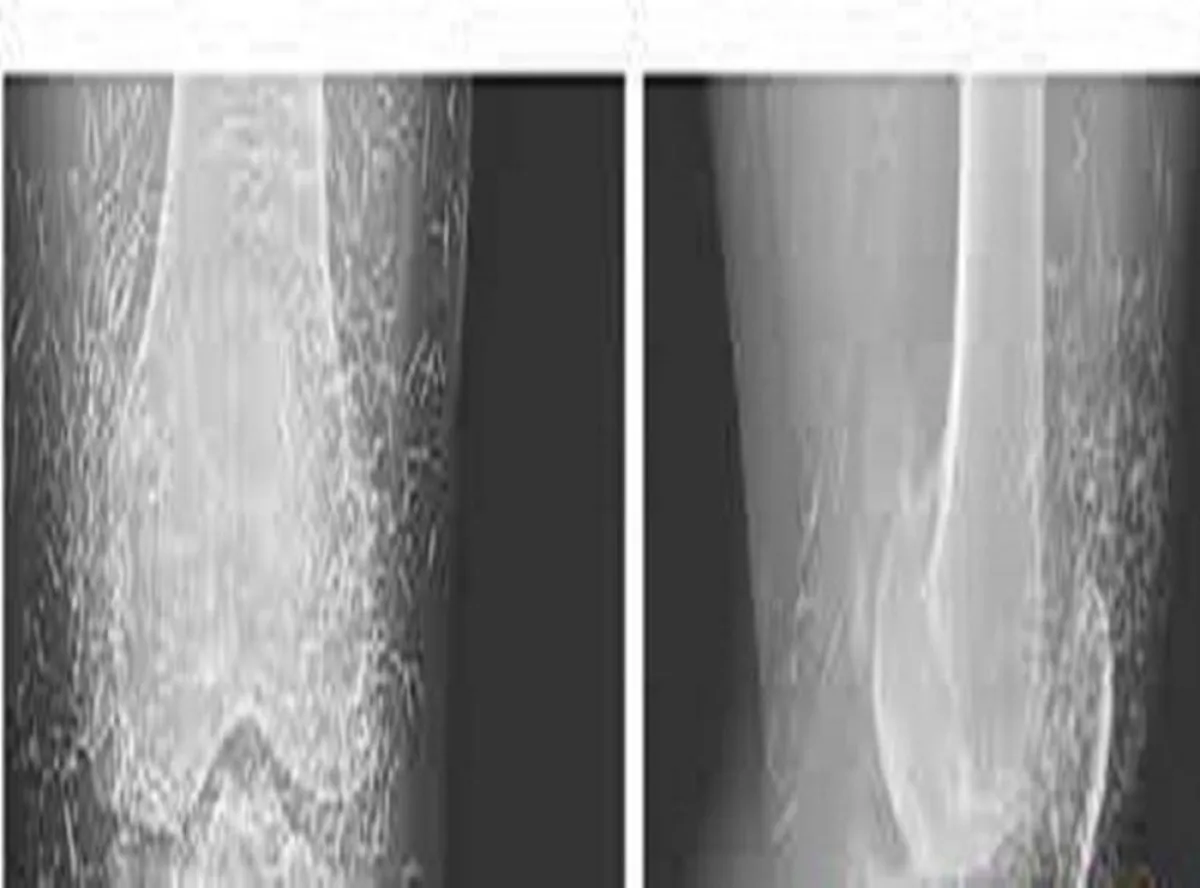

عندما قام الأطباء بإجراء صورة بالأشعة السينية لركبة امرأة تعاني من آلام حادة في المفاصل لم يتوقعوا أن يكون الذهب هو سبب هذا الألم الذي تعاني منه؛ حيث عثروا على معدن من الذهب كان عبارة عن مئات من إبر الوخز الصغيرة التي بقيت في أنسجتها.

الغريب في الأمر أنّ الإبر التي يعتقد أنها من "الذهب" تركت عمداً في أنسجة المريضة لتواصل تحفيزها.